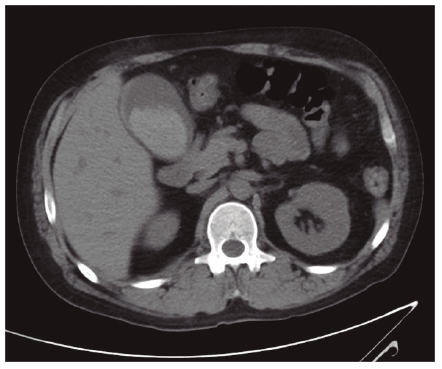

Presentamos el caso de un paciente que sufre un traumatismo abdominal cerrado por coz de caballo observándose en pruebas de imagen engrosamiento de la pared de la vesícula biliar con contenido hemorrágico como único hallazgo, sin otras lesiones asociadas intraabdominales.

Paciente de 38 años sin antecedentes personales de interés que acude a Urgencias por traumatismo abdominal cerrado por coz de caballo. A su llegada a nuestro Centro se encuentra estable hemodinamicamente. A la exploración destaca dolor a la palpación en hipocondrio derecho sin signos de irritación peritoneal. Se solicita analítica en la que destaca cifra de hemoglobina de 11,9 g/dL y transaminasas levemente elevadas, no constaban analíticas previas. Ante la estabilidad del paciente se solicita ecografía (Figuras 1 y 2) que se completa con TAC (Figura 3).